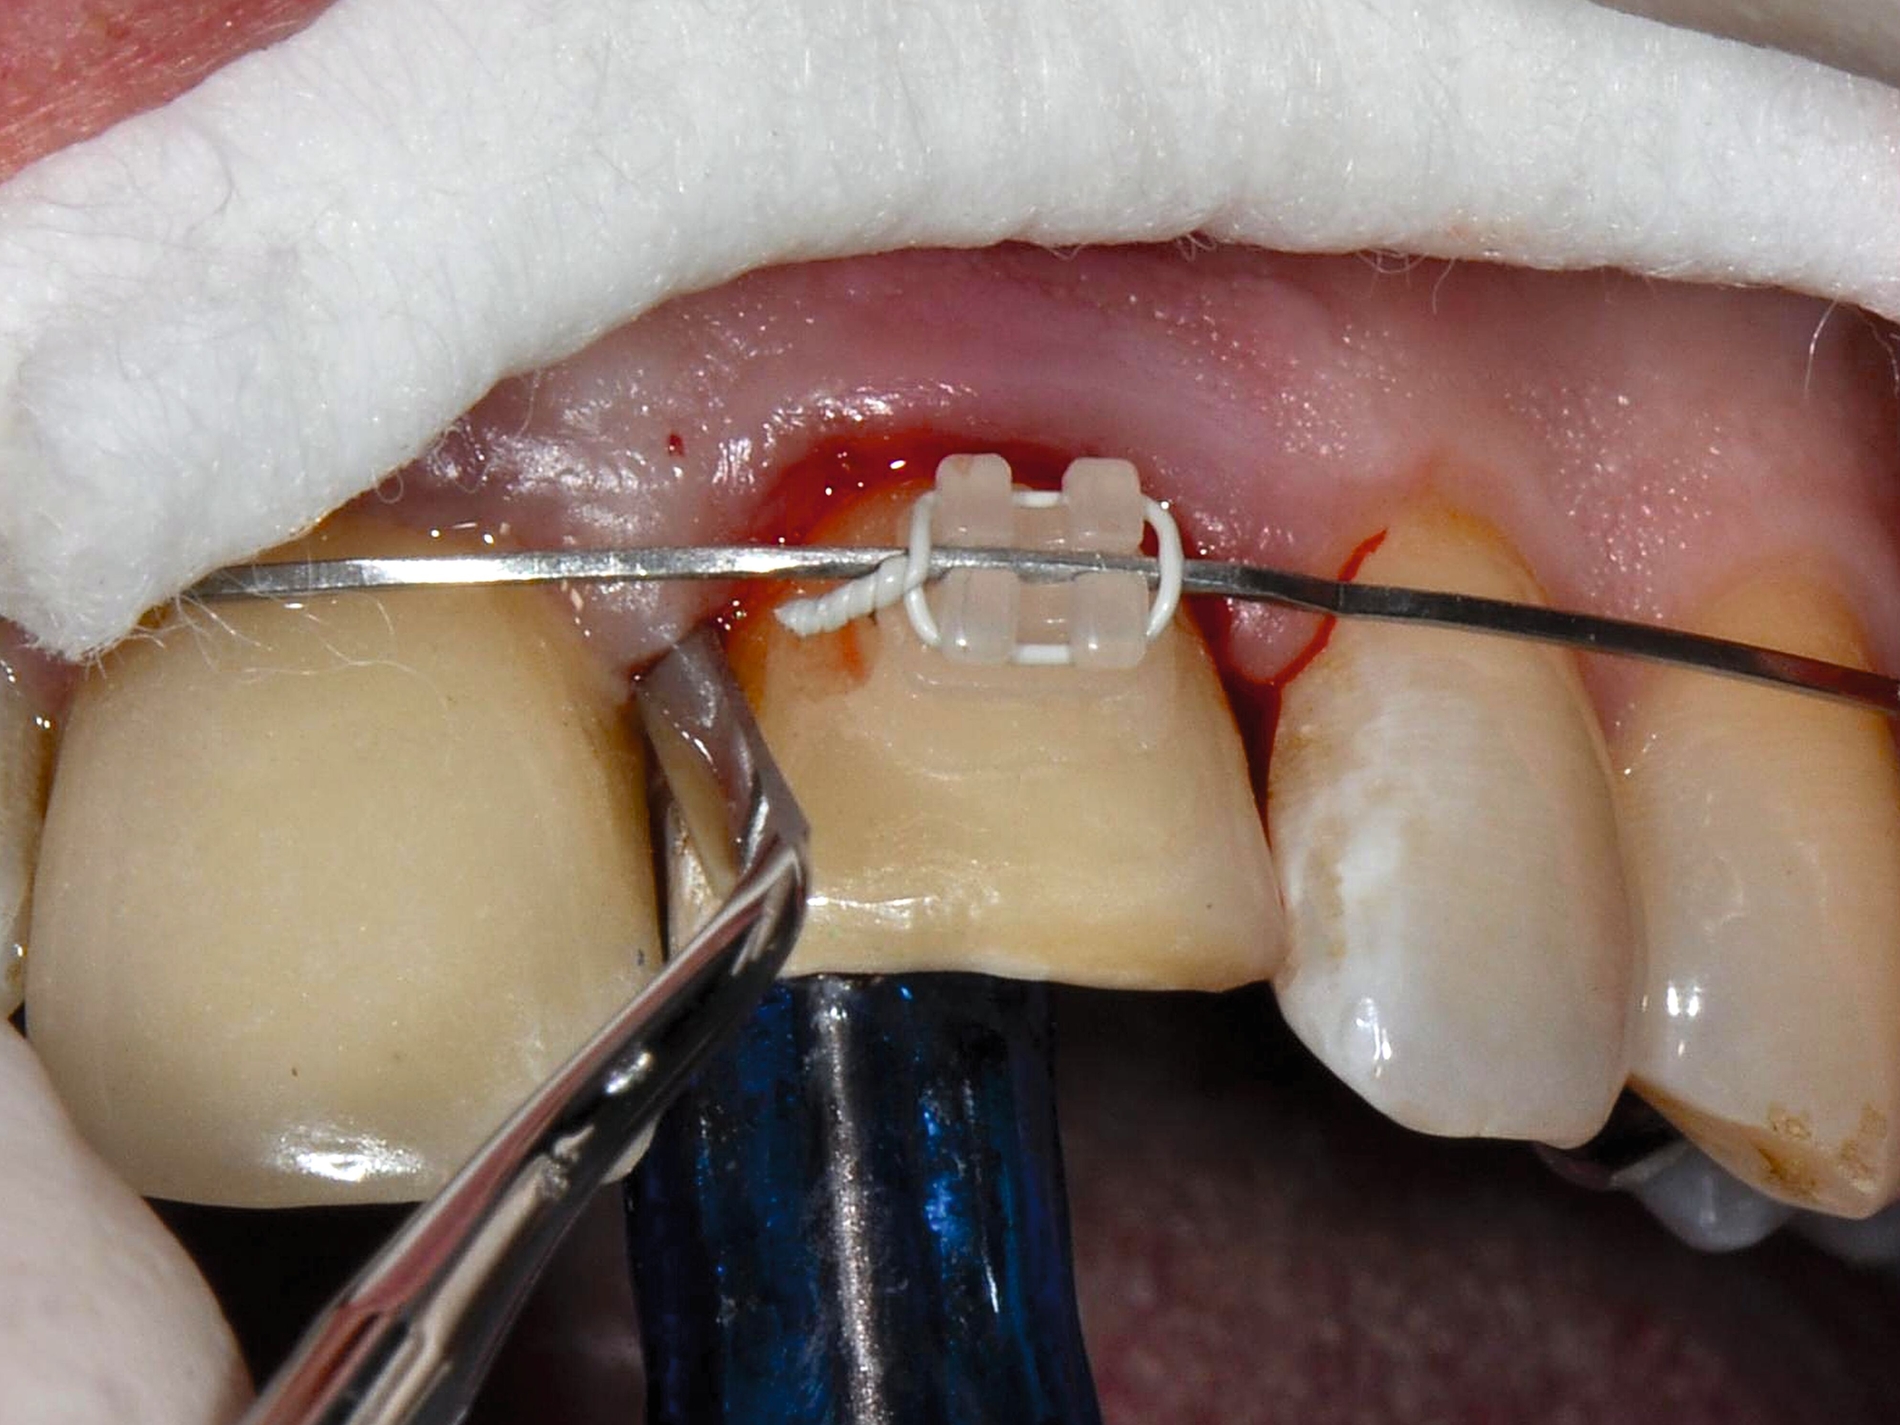

Scheint nach Kronen-Wurzel-Frakturen der Zahnerhalt grundsätzlich möglich, stehen verschiedene Behandlungsalternativen zur Verfügung, die maßgeblich davon abhängen, ob die Defektlokalisation eine suffiziente restaurative Versorgung zulässt beziehungsweise mit welchen Mitteln diese erreicht werden kann [Krastl et al., 2011]. Neben der adhäsiven Fragmentbefestigung, der restaurativen Versorgung der zugänglichen supragingivalen Bereiche, der restaurativen Versorgung nach chirurgischer Kronenverlängerung oder chirurgischer Extrusion kann auch eine restaurative Versorgung durch eine vorherige kieferorthopädische Extrusion ermöglicht werden.

Im Hinblick auf Kronen-Wurzel-Frakturen beziehungsweise zervikale Wurzelfrakturen stellt die kieferorthopädische Extrusion eine schonende Behandlung von Vorteil dar, da bei schneller Extrusion die Gingivahöhe erhalten bleibt. Prapas et al. unterscheiden hierbei die klassische langsame kieferorthopädische Extrusion (maximal 1-2 mm pro Monat) durch leichte Kräfte und die schnelle Extrusion, bei der der Zahn mit starken Kräften aus der Alveole bewegt wird (3-4 mm pro Monat) [Prapas et al., 2008]. Während bei der langsamen Extrusion Alveolarknochen und Weichgewebe dem Zahn in gleichem Ausmaß zu folgen scheinen, bleiben bei der schnellen Extrusion die umgebenden Gewebe weitgehend zurück [Prapas et al., 2008].

Um bei einer schnellen kieferorthopädischen Extrusion sicherzustellen, dass keine limbale Knochenapposition durch eine Mitwanderung der Gingiva erfolgt, sollte dabei in regelmäßigen Abständen eine suprakrestale Fibrotomie durchgeführt werden [Carvalho et al., 2006]. Wird bei der kieferorthopädischen Extrusion keine regelmäßige suprakrestale Fibrotomie durchgeführt, kommt es auch zu einer Koronalverlagerung von Gingiva und Knochen. Dies ist bei einer nachfolgend angestrebten restaurativen Versorgung, die die Frakturränder in der Restauration fassen soll, in der Regel nicht erwünscht [Carvalho et al., 2006].

Schnelle kieferorthopädische Extrusionen im Sinne einer präprothetischen Maßnahme können zudem auch im Seitenzahnbereich indiziert sein, wenn für eine nachfolgende Kronenversorgung die notwendigen Voraussetzungen geschaffen werden sollen (ausreichende Stumpfhöhe, Einhaltung der biologischen Breite, Schaffung des Ferrule-Designs) [Gariulo et al., 1961; Juloski et al., 2012; Nugala et al., 2012] unter Einhalten eines Kronen-Wurzel-Verhältnisses von 1:1 [Grossmann und Sadan, 2005] (Abbildung 3).